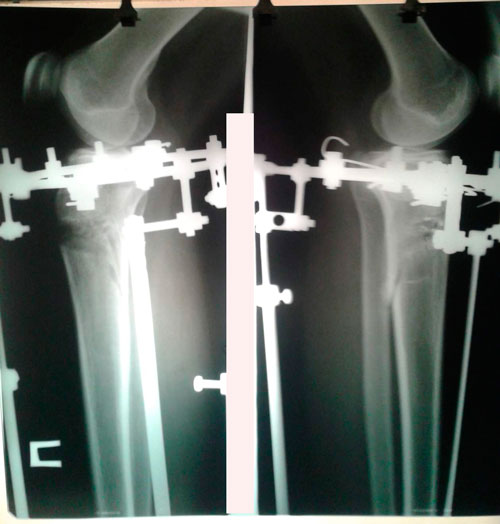

Исходник - 35 лет.

Укорочение правой ноги - 2 см.

Левая голень более деформирована.

Дата операции 22.03.2016г.

Дата снятия аппаратов 22.06.2016г.

Срок лечения 90 дней.

Диагноз: Укорочение правой ноги - 2 см.